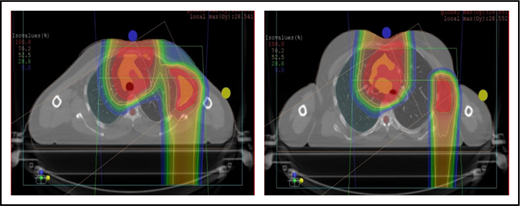

Proton therapy can significantly reduce the radiation dose to the breasts by specifically using fields that enter posteriorly and stop short of exiting through the breast. Alternatively, if protons cannot be used, other methods of displacing the breast can be used instead, such as using an inclined board or physically moving the breast out the beam path. Figure 3A shows how using proton therapy can spare the breast in a case with axillary involvement.

Axillary involvement at presentation. (A) Axial, coronal, and sagittal views of a proton plan (left) and an IMRT plan (right) for a patient presenting with axillary involvement. Use of proton therapy in this case spares the left breast. (B) Regardless of which treatment modality is chosen, IMRT (left panel) and proton (right panel), limiting the volume exposed to radiation should include attention to avoiding a low-dose bath. (C) Limiting lung dose. If avoiding the lung is the primary objective in a given patient, especially if the patient has received pulmonary toxic chemotherapy (eg, any combination of bleomycin, busulfan, gemcitabine, brentuximab, etc.), proton therapy may better spare the lungs by reducing the low-dose bath seen with photons.

Consideration of lung dose

With the advent of CT-based planning for mediastinal lymphoma, the dose to the lungs can now be correlated with the risk for pneumonitis. Restrictions on lung dose are encouraged to be V5 < 55%, mean lung dose < 13.5 Gy, and V30 < 20%. These values are more attainable with the use of DIBH.38 Although a mean lung dose of 13.5 Gy has been associated with a lower risk for pneumonitis, it is advisable to aim for a lower dose, which is quite often attainable when strict constraints are used. For example, when IMRT is used, it is important to limit the beams to some variation of anteroposterior beams, avoiding lateral beams. If avoiding the lung is the primary objective for a given patient, especially if that patient has received pulmonary-toxic chemotherapy (eg, bleomycin, busulfan, gemcitabine, brentuximab), proton therapy may better spare the lungs by reducing the low-dose bath seen with photons (Figure 3C).